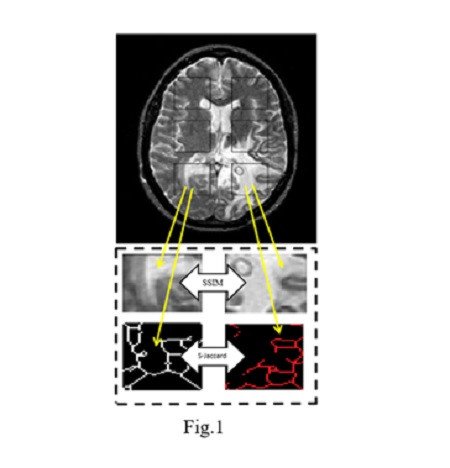

S-a generat o bază de date mare de imagini T2w și PD aparținând unor pacienți sănătoși și pacienți diagnosticați cu gliom. Similaritatea structurală a fost evaluată folosind valorile indicelui SSIM (Structural Similarity Index) și un nou indice propus de noi, S-Jaccard (Skeleton Jaccard). Fiecărei imagine i s-a aplicat o structură de măști de formă dreptunghiulară (35 x 45 pixeli), care a fost proiectată în emisfera dreaptă și apoi reflectată în oglindă în emisfera stângă. Prin acest procedeu au fost decupate 528 de regiuni de interes (264 pentru imagini cu pacienți bolnavi și 264 pentru imagini cu pacienți sănătoși), obținându-se valorile indicilor de similaritate SSIM, S-Jaccard.

Exemplificăm folosind o imagine RMN în mod T2w a unui cu gliom cerebral, cu evidențierea suprapunerii măștii pe țesutul cerebral, decuparea regiunilor de interes monocromatice pentru calcularea SSIM, aplicarea algoritmul de scheletonizare pe același regiunile de interes pentru calcularea S-Jacard. Valorile celor doi indici de similaritate au fost grupate folosind un algoritm de grupare dedicat și comparate.